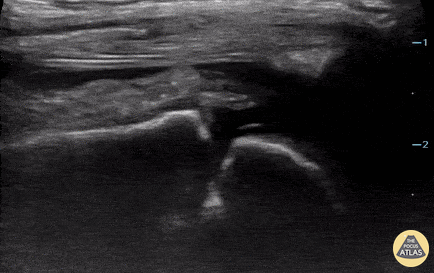

2 year-old male presented with fever, right knee swelling, and elevated CBC, CRP and ESR. POCUS revealed a right knee effusion. Paul Khalil, MD. Assistant PEM POCUS director at University of Louisville/Norton Children’s @khalil3paul